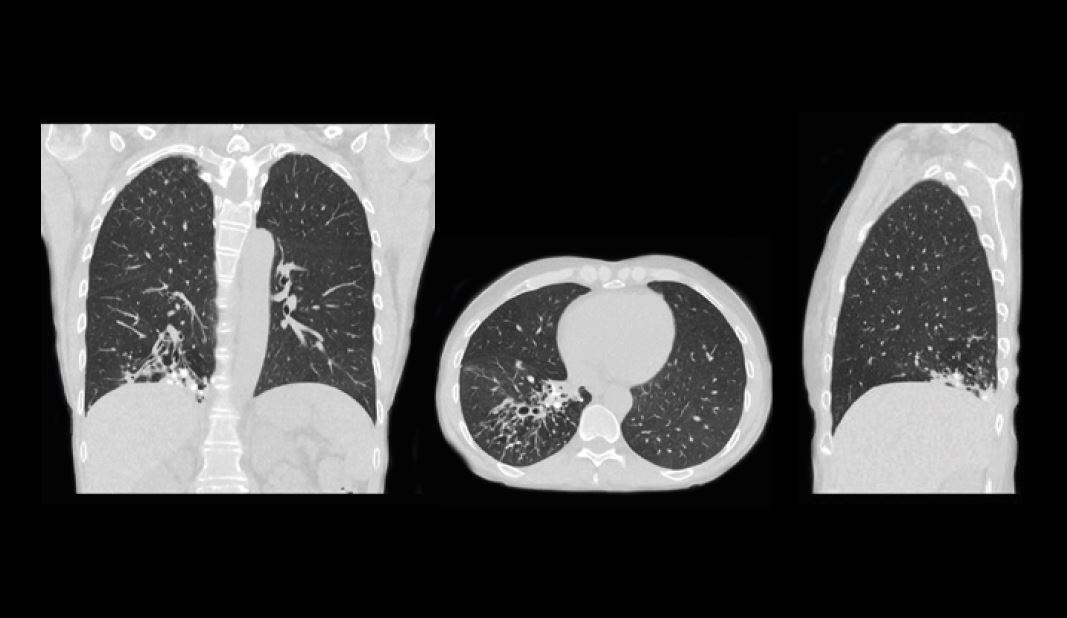

КТ легень, отримана за допомогою техніки SilverBeam, CTDIvol 0,4 / DLP 18,7.